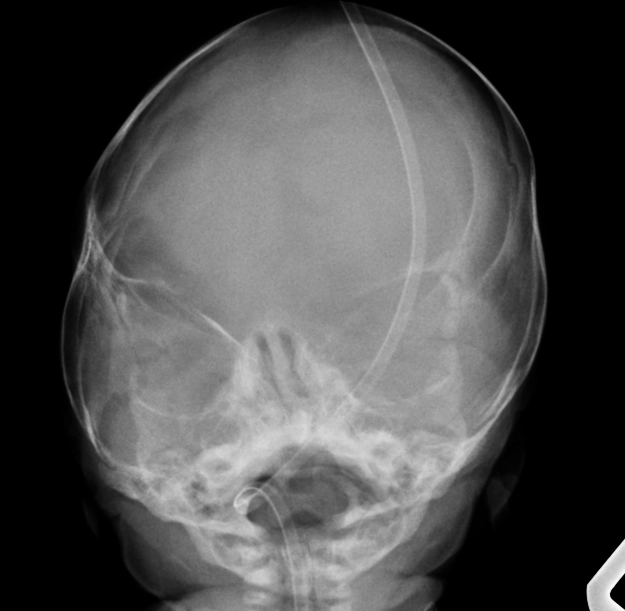

• Thoát vị não-màng não đỉnh dạng thoái triển (Atretic parietal cephaloceles)

Thoát vị não-màng não đỉnh dạng thoái triển (Atretic parietal cephaloceles)

• Thoát vị màng não thoái triển thai nhi (Atretic cephalocele)